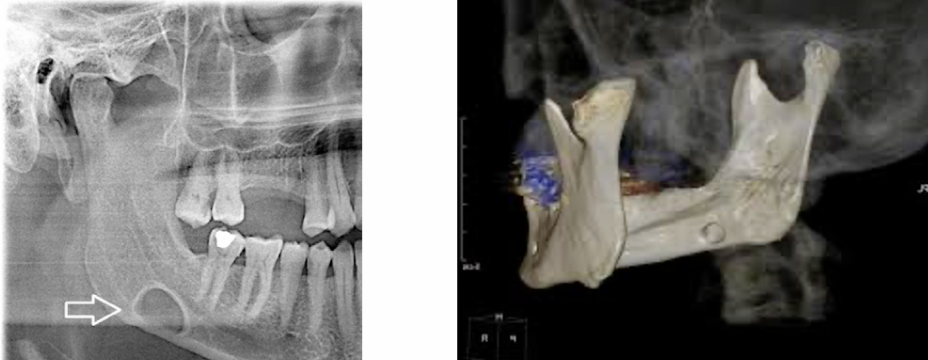

what is this?

Stafne’s Idiopathic Bone Cavity

- looks like a cyst but isnt

- always in the posterior mandible

- usually below the IAD

• well define with an opaque margin

• doesn’t move or change shape in monitoring pics

• caused by an indentation of the sublingual salivary gland